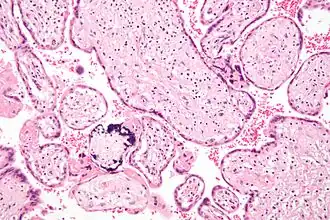

![]() Микрофотография плацентарной инфекции (плацентарный ЦМВ) | |

Инфекцию можно выявить микроскопически путём обнаружения внутриядерных включений. При окраске гематоксилин-эозином тельца включений становятся темно-розовыми, их называют «совиными глазами»[9].

Иллюстрации

Микрофотография цитомегаловирусного плацентита.